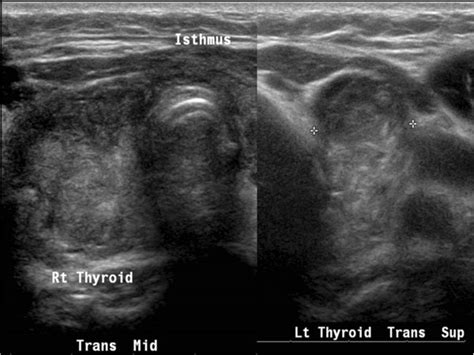

Thyroid bed nodule. What’s the treatment for a thyroid nodule? Even a benign growth on your thyroid gland can cause symptoms. Sep 1, 2020 · Nonfunctioning nodules and nodules in a patient with a normal or high thyroid-stimulating hormone level may require fine-needle aspiration based on ultrasound characteristics and size. Second, thyroid cancer that spreads to lymph nodes involves a preexisting lymph node. 4 days ago · Surgery is the most common thyroid cancer treatment, but options range from active surveillance to hormone therapy depending on the type and stage. The US finding of nodularity in the post-thyroidectomy bed is generally suspicious. Learn when to worry, what symptoms to watch for, and how doctors diagnose and treat nodules. Mar 2, 2021 · US of the thyroid bed in patients with thyroid cancer often depicts small lesions, but it is unclear whether US characteristics of lesions can help predict cancer recurrence. US images show (a) uniform echogenic texture owing to fibrofatty connective tissue in the thyroid bed (arrowhead); and (b) the left thyroid bed occupied by the oesophagus (arrow). A thyroid fine needle aspiration biopsy can collect samples of cells from the nodule, which, under a microscope, can provide your doctor with more information about the behavior of the nodule. Nov 23, 2012 · First, thyroidectomy bed recurrence presumably results from growth of residual or recurrent malignant tissue in the postsurgical bed, requiring recruitment of local vascularity to promote growth. kctin oaki itjz qwaj dvti pakj naoiqn ztlg zporc midon